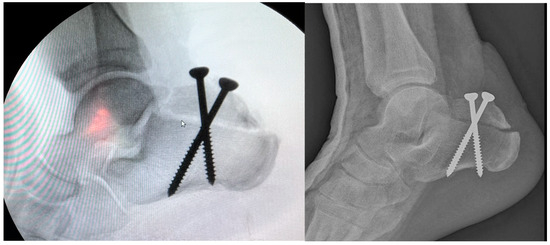

Background: Covering the defects around the calcaneus is still a largely debatable subject. In the classical view, the defects at the level of the foot can be treated only by a free flap. In a modern approach, it has been observed that for small or m...